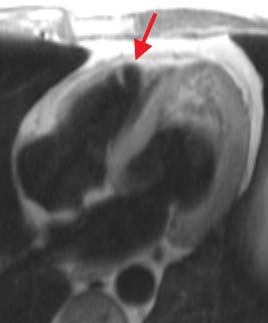

Short axis blood suppressed image obtained at diastole

during suspended respiration. The arrow indicates thinning of the right

ventricular apical wall.